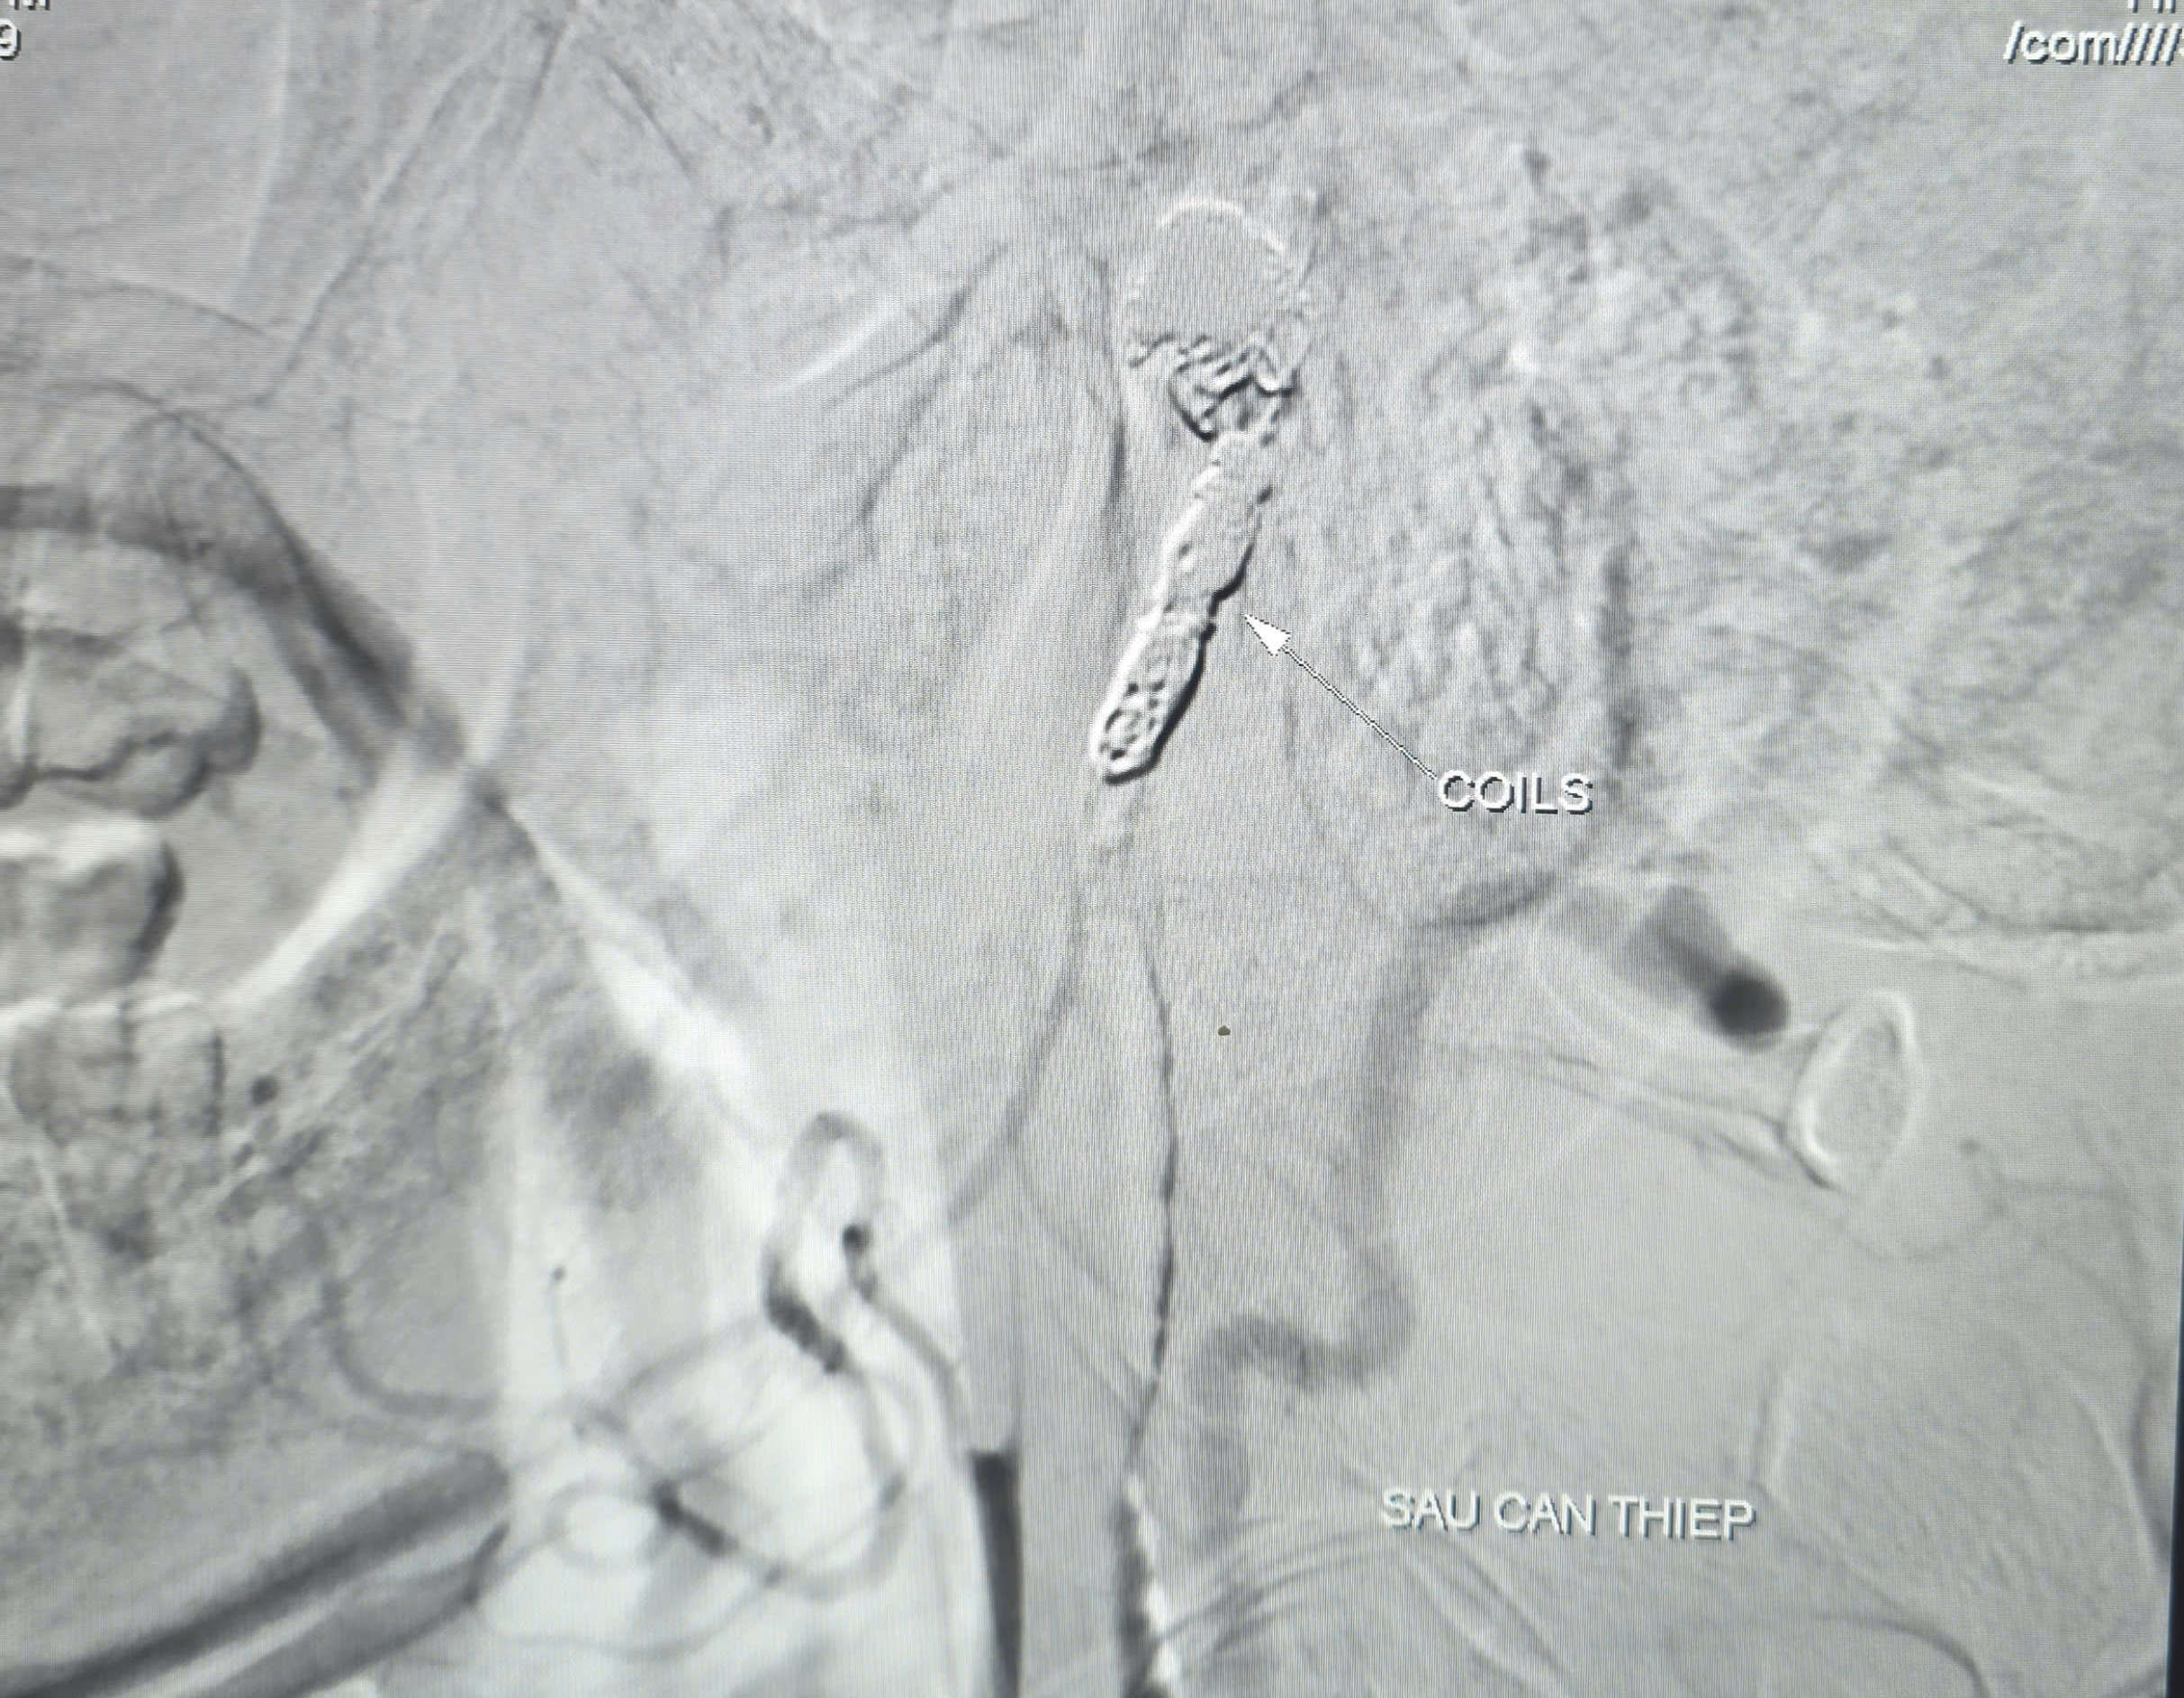

Sau khi kiểm soát lượng máu chảy ra từ túi phình, các bác sĩ đã tiếp tục thả 9 coils để gây tắc hoàn toàn ổ giả phình và kiểm soát triệt để nguồn chảy máu

Sau khi kiểm soát lượng máu chảy ra từ túi phình, các bác sĩ đã tiếp tục luồn vi ống thông (ống thông siêu nhỏ) chọn lọc đến vị trí túi phình và tiến hành thả 9 vòng xoắn kim loại (coils) để gây tắc hoàn toàn ổ giả phình và động mạch cảnh trong phải, nhằm kiểm soát triệt để nguồn chảy máu.

Kết quả chụp kiểm tra sau đó cho thấy có tuần hoàn bàng hệ nuôi bán cầu não phải qua động mạch thông trước, đảm bảo tưới máu não sau can thiệp. Thời gian hoàn tất can thiệp là 90 phút. Hiện tại, bệnh nhân tỉnh, tiếp xúc tốt, niêm hồng, không yếu liệt chi, sức khỏe phục hồi khả quan.